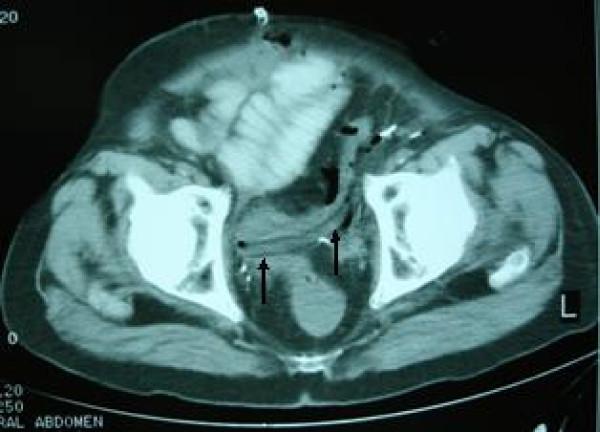

We describe a case of perforation of the large bowel caused by the drain tube placed in a 74-year-old patient who had undergone radical cystectomy for invasive bladder cancer.

我们描述了一例74岁患者的大肠穿孔病例,该患者因浸润性膀胱癌接受了根治性膀胱切除术,穿孔由放置的引流管所致。